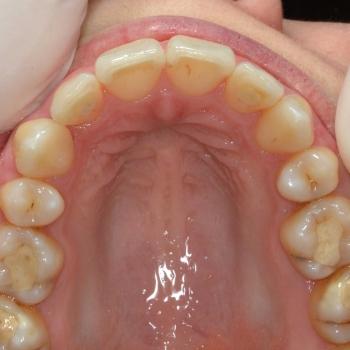

Tünde a felső fogív torlódása, illetve az alsó metszőfogak között található rések miatt keresett fel. Az első találkozásunk alkalmával azonban fény derült a középvonalak eltolódására, enyhe mélyharapásra, a felső metszőfogak túlzott elülső pozíciójára, illetve a régóta hiányzó alsó 6-os fog helyének beszűkülésére is, így a kezelési terv ezen problémák megoldására is kitért.

Tünde végül úgy döntött, hogy nem csak az esztétikai, de a funkciós problémák is szeretné megoldani, melyhez hagyományos fém fogszabályozót választott. A fogszabályozáshoz különböző kiegészítőket is igénybe vettünk úgy, mint harapásemelő, különböző intermaxillaris gumihúzások, illetve egy speciális szájpadi mini-implantátum a hozzá kapcsolódó transpalatinalis ívvel (hibrid transpalatinal ív), ami minimalizálta a hátsó fogak mozgását, miközben a felső metszőfogak hátrafele mozogtak.

A kezelés végére minden problémát sikerült megoldanunk, a középvonalak korrekcióját leszámítva. Ennek ellenére, mivel a felső középvonal az arc tengelyében helyezkedik el, az esztétikai eredmény nem csorbult és a funkciót sem befolyásolta. A jobb alsó 6-os fog implantációs pótlása a fogszabályozás befejeztével kezdődött meg.